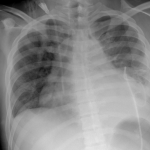

Setahun yang lalu, kita lihat ramai warga tua yang dijangkiti penyakit Covid-19 dan ramai di kalangan mereka ini meninggal dunia disebabkan komplikasi Covid-19 serta masalah kesihatan sediada. Kini kita lihat ramai yang muda masuk ke wad disebabkan jangkitan Covid-19. Ada di antara mereka ini tidak mempunyai sebarang sejarah kesihatan, dalam erti kata lain -`sihat’. Ramai yang kecundang dalam melawan jangkitan ini. Wanita hamil mempunyai risiko kematian 1.8-2.5 kali ganda berbanding dengan populasi umum. Kebanyakan wanita yang dimasukkan di wad memerlukan bantuan oksigen. Imbasan X-ray paru-paru menunjukkan jangkitan Covid-19 telah menyerang paru-paru mereka menyebabkan mereka menghadapi kesukaran untuk bernafas. Adakalanya inflamasi yang dihasilkan oleh virus tersebut menyebabkan saluran darah menjadi tidak normal serta cenderung kepada pembentukan darah beku yang kecil yang boleh menyebabkan kegagalan buah pinggang. Bila ini terjadi, adakalanya sukar diubati. Ini kerana sehingga kini, tiada ubat yang mampu membunuh virus tersebut. Virus merupakan sejenis makluk yang mampu merubah bentuk untuk melawan persekitaran yang tidak kondusif baginya. Ia akan berubah untuk menjadi lebih kuat untuk kelangsungan hidupnya.